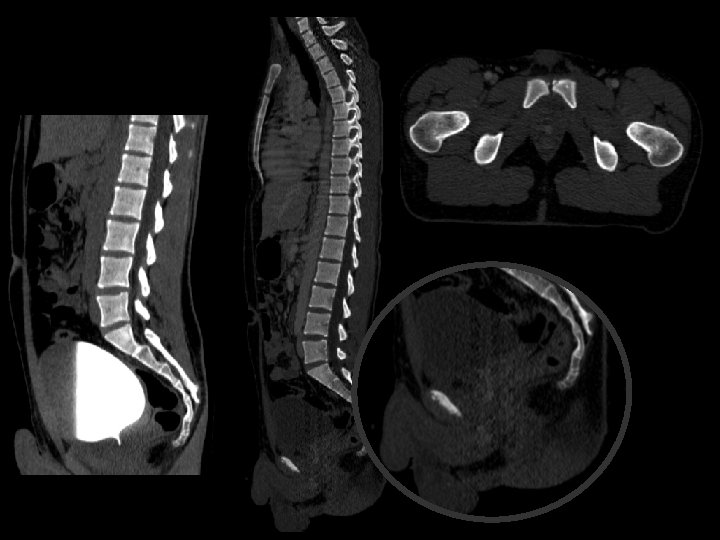

Ureterorragia = Trauma uretral? Estudio dirigido!

Extravasación del contraste con disrupción de la uretra membranosa posterior Compromiso parcial del diafragma urogenital.

Determinar sitio de disrupción/ruptura Compromiso vejiga? Ver: extravasación Fracturas de pelvis + frec hombres Tipo 3 injurias posterior 20% afectacion vejiga

TIPO 1 Estiramiento posterior de la uretra. Diastasis del pubis. TIPO 2 Ruptura de uretra posterior por debajo de diafragma (sin lesión)

TIPO 3 Ruptura uretra posterior y diafragma. extravasación por uretra membranosa. TIPO 4 Contraste extraperitoneal. Ruptura de vejiga. Hematoma perivesical Distasis de pubis

Conclusión Complicacion frecuente en trauma pelvico! 24 % en fx. Buscar trauma uretral y que tipo es? Conocer la anatomía y los métodos. Determinar grado de trauma y sus complicaciones.